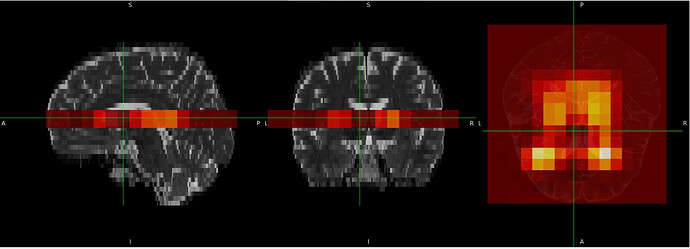

I am currently working on Siemens .rda data acquired on an XA20 system and I am trying to generate voxel masks. I have been struggling with this for a while, and because of an issue I encountered, I opened this thread where @mmikkel kindly tried to help. After re-examining both the code and the generated masks, I realized that although the voxel position is correct, the orientation is inverted in all directions (can be seen when comparing the scanner image with the generated voxel mask bellow). Initially, I thought the problem was limited to the axial plane, but it turns out that all orientations are flipped.

This is the data viewed in the World coordinates Display space (which is aligned with the scanner’s gradient frame)

where an orientation is obvious. When we switch to the structural image sub1_Bet space with the same data, we see most of the orientation disappear in both: